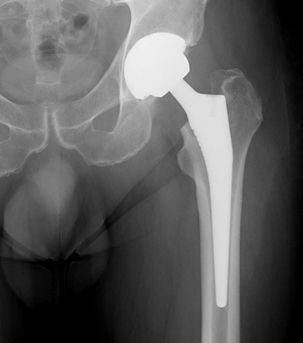

xray of a successful Total Hip ReplacementTotal Hip Replacement is an effective procedure that reduces pain, increases function and increases quality of life.

There are many different types of hip replacement in common use today such as cemented or uncemented types with a variety of bearing surfaces such as metal, polyethylene and ceramics. Each particular type has its own advantages and disadvantages and these can be discussed in detail with Mr Seyi Idowu during your consultation. The choice of implant is made on several factors which can be discussed during your consultation.